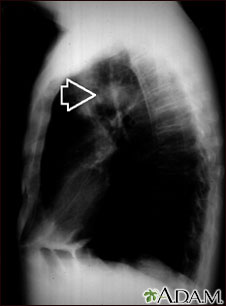

This individual has a mass in the upper part of the lung. Although the cause of the mass can be suspected, based on this person's history, there are many diseases that can produce lung lesions.